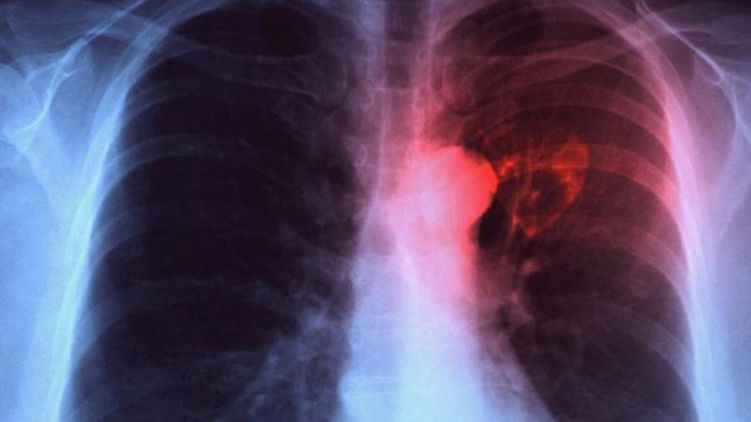

Минздрав предрек Украине вспышку туберкулеза

Если сложная ситуация с финансированием медучереждений не изменится в ближайшее время в Украине случится вспышка туберкулеза. Дефицит бюджета противотуберкулезных больниц доходит до 80%.

Напомним, что за первые два месяца 2020 года от туберкулеза в Украине умер 581 человек.